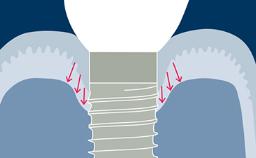

Existem muitas opções convencionais de tratamento fixo que podem ser consideradas para a substituição de dentes ausentes. Incluindo Próteses Dentárias Fixas ou PDFs, PDFs com cantilever e PDFs adesivas. A escolha da opção de tratamento deve levar em conta os desejos do paciente e as necessidades percebidas. O tratamento deve ser guiado pelo planejamento da prótese. Quando mais de uma opção prostética é possível, os resultados do tratamento publicados na literatura científica devem ser considerados e usados como um fator para aconselhar o paciente sobre a opção mais adequada. Este módulo discutirá as vantagens e desvantagens das opções convencionais de tratamento fixo para substituir os dentes ausentes e comparar os resultados e as indicações de tratamento publicados com as de próteses fixas implantossuportadas.